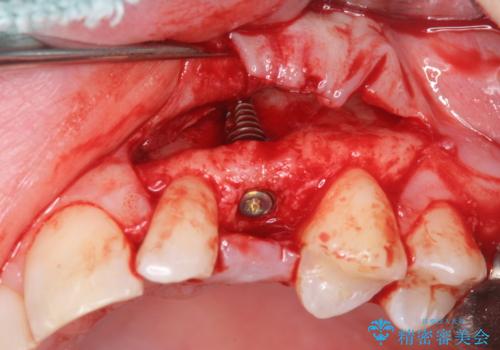

骨造成を伴う 前歯部インプラント治療

適切なインプラント埋入を行い、不足している骨量を補うため骨の造成を併用したインプラント治療を計画します。

前歯のインプラント治療は骨量・歯肉の厚み・インプラントの方向をしっかりと計画することで、審美的で長持ちを期待できるような仕上がりとなります。